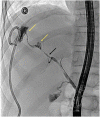

Blunt abdominal trauma is a common cause of solid organ injury in children. Nonoperative management has been established as the standard of care for suspected liver and spleen injuries without peritonitis. Major ductal injury with resultant biloma is a rare complication of nonoperative management of blunt liver injury. Endoscopic retrograde cholangiopancreatography (ERCP) and/or percutaneous drain placement are considered to be safe adjuncts in the management of these bile leaks. However, in the rare cases of persistent bile leak, further nonoperative alternatives have not been reported. In this case report we present a novel multidisciplinary approach to managing persistent bile leaks in blunt liver injury.